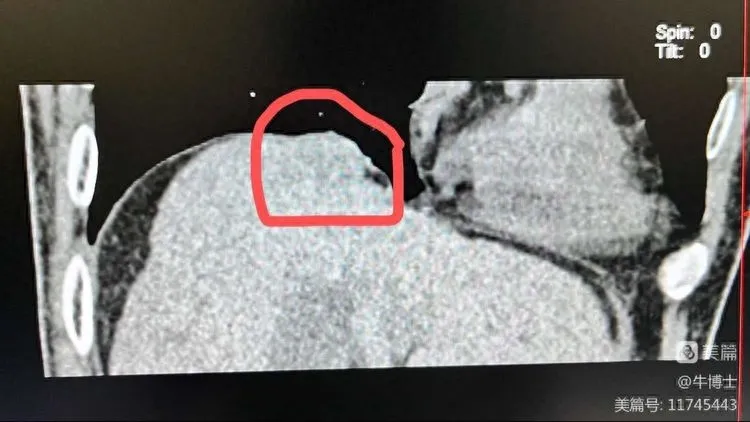

隔顶部肝肿瘤

在消融前建立人工气胸,通过空气隔离的技术消除消融如邻近纵隔、心脏及大血管的胸部肿瘤以及邻近膈肌的肝顶部肿瘤等盲区,形成足够的安全穿刺空间,以便顺利完成肿瘤的完全消融治疗。同时,在影像技术引导下具有定位精确、图像整体性好及显示穿刺针、进针路径、肿瘤与瘤旁脏器关系的优势,能够为患者提高完全消融率及有效减少并发症发生。

▲利用肝导向入路seldinger技术,在人工气胸下行膈顶肝癌冷冻消融术。